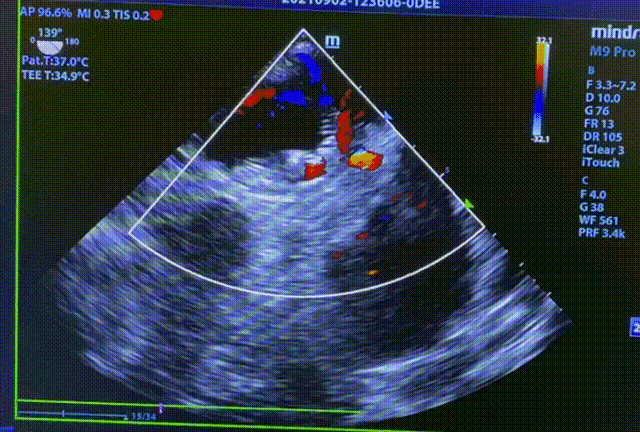

常规肝位造影显示,左心耳锚定区约26mm, 开口约29mm, 因此选择型号为LT-LAA-2834的LAmbre™左心耳封堵器对患者实施封堵。LAmbre™植入过程一步到位,U型钩均完全展开。随后复查造影及TEE结果,封堵盘呈“碗状”形态完美贴合于左心耳口部,无残余分流,牵拉测试稳定,综合评估符合COST原则,随后完美释放,封堵效果理想。术后,患者各项指标正常,身体恢复良好。

释放后TEE检查(135°)